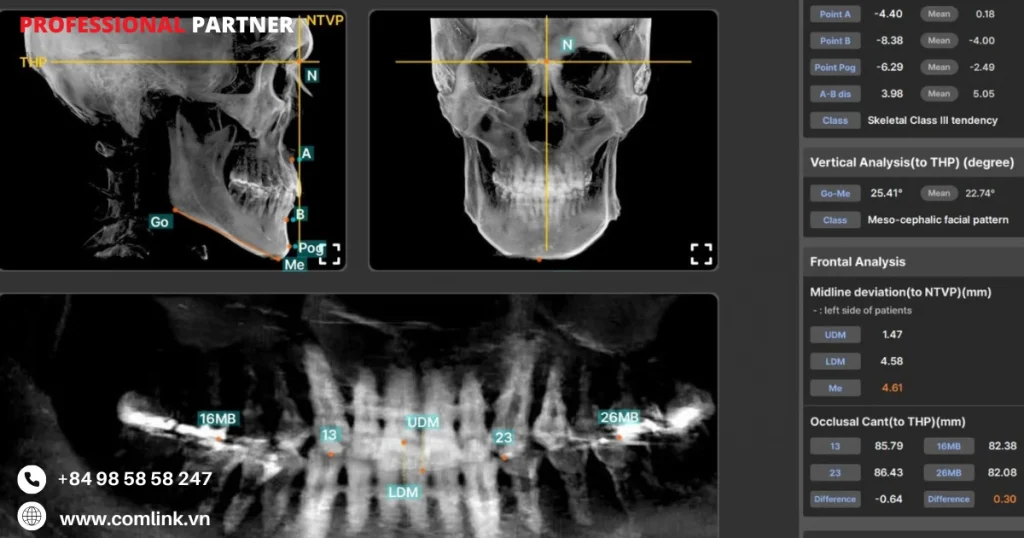

Phần mềm AIciti là một giải pháp cải tiến dựa trên AI được thiết kế để tăng cường phân tích hình ảnh nha khoa và lập kế hoạch điều trị.

Tận dụng các thuật toán AI tiên tiến, AIciti tự động hóa việc xử lý và giải thích hình ảnh CBCT 3D.

Vì vậy cung cấp những thông tin chi tiết về cấu trúc nha khoa và hỗ trợ các chuyên gia nha khoa đưa ra quyết định chính xác.

Xử lý hình ảnh tự động

- Phần mềm AIciti tự động hóa việc phân tích hình ảnh CBCT, trích xuất các điểm dữ liệu có liên quan.

- Vì vậy tạo ra các biểu diễn trực quan về các cấu trúc giải phẫu quan trọng.

Tạo mặt phẳng tham chiếu

- Phần mềm tự động tạo các mặt phẳng tham chiếu trực quan hóa mối quan hệ trước-sau của xương hàm, độ nhô của răng và tính đối xứng của khuôn mặt.

- Điều này hỗ trợ các bác sỹ lập kế hoạch và đánh giá điều trị.

Thông tin chi tiết về chẩn đoán

- AIciti cung cấp cho bác sĩ lâm sàng thông tin chi tiết về chẩn đoán dựa trên phân tích do AI điều khiển.

- Từ đó giúp họ xác định các bất thường, đánh giá mật độ xương và phát hiện các bất thường về cấu trúc một cách chính xác.